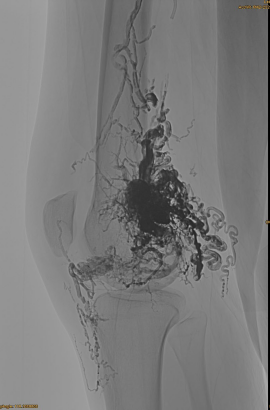

Основная информация пациента: женщина, 36 лет; Avm таз, бедра, колено, левое osg, множественные предварительны - эмболизация.

Используемые продукты: 3PCS LAVA-34,14PCS LAVA-18.

Начальный DSA:

Окончательный результат:

Вряд ли какой -либо венозный отток:

Поздняя фаза, еще один эмбо, но намного лучше: